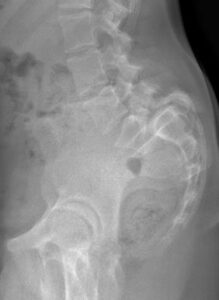

Le spondylolisthesis L5 est un glissement en avant de la 5° vertèbre lombaire par rapport au sacrum. Le glissement est du à une fracture progressive (lyse) à la jonction (isthme) entre la partie antérieure et la partie postérieure de la 5° vertèbre. D’où le nom de spondylolisthésis par lyse isthmique.

Spondylolisthésis instable